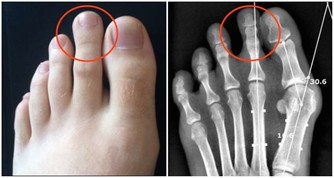

紅酒有助於腎臟排泄尿酸和預防痛風、風濕病和關節炎。